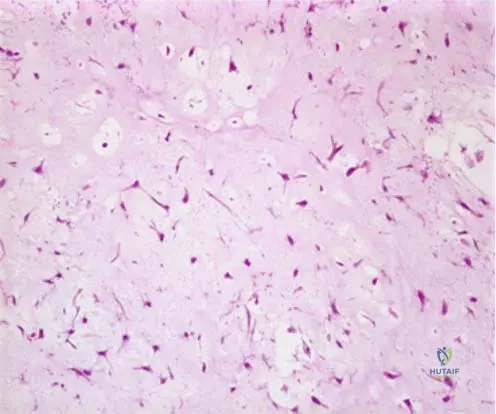

Rationale: The clinical text accompanying Fig. 8.106b states, "Higher power view (b) of primary lymphoma of bone. Note the round or oval appearing nuclei, which appear vesicular, owing to the margination of chromatin at the nuclear membrane. Nucleoli may be single and central, or may number two or three and be located adjacent to the nuclear membrane." This description is specific to lymphoma cells. Chondroblastic cells, osteoblastic cells, and fibroblasts have distinct nuclear and cytoplasmic features. Giant cell tumor stromal cells have oval nuclei but lack the specific chromatin margination described.

Rationale: The description provided in the vignette and Fig. 8.106 refers to the characteristic nuclear features of the neoplastic lymphocytes found in lymphoma. The text states, "Note the round or oval appearing nuclei, which appear vesicular, owing to the margination of chromatin at the nuclear membrane. Nucleoli may be single and central, or may number two or three and be located adjacent to the nuclear membrane." These are features of the malignant B-cells. Osteoblasts, chondrocytes, fibroblasts, and adipocytes have distinct morphological characteristics.

Correct Answer: B

Rationale: The clinical context for Fig. 8.51 explicitly describes the higher power photomicrograph showing "myxoid/chondroid stroma and lobules of spindle shaped or stellate cells with abundant myxoid or chondroid intercellular material." This directly matches option B. The other options describe features of other tumors (e.g., clear cell chondrosarcoma, giant cell tumor, chondrosarcoma, osteoblastoma/osteosarcoma).

Rationale: The higher power photomicrograph (Fig. 8.51) of chondromyxoid fibroma characteristically shows lobules of spindle-shaped or stellate cells with abundant myxoid or chondroid intercellular material. This is a defining histological feature. Option C describes Giant Cell Tumor, while Option A describes epithelioid sarcoma or similar lesions not typical for CMF. Option D describes normal bone marrow or lipoma. Option E describes osteochondroma. The main distractor, C, describes a Giant Cell Tumor, which can also present as a lytic lesion in a young adult, but has distinct histological features.

Rationale: The higher power photomicrograph (Fig. 8.51) and its context describe "myxoid/chondroid stroma and lobules of spindle shaped or stellate cells with abundant myxoid or chondroid intercellular material." This is the most characteristic high-power histological feature. The main distractor, A (Presence of numerous osteoclast-like giant cells), describes a Giant Cell Tumor, which can be a differential but has distinct stromal cells.